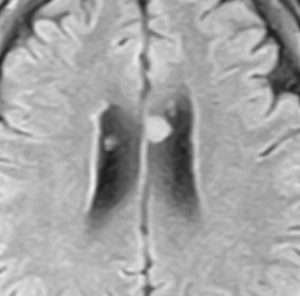

多発性のもの

45歳で偶然に発見されたものです。上衣下腫の多発例というより,T1は等信号でガドリニウム増強されません。軽症の結節性硬化症 tubrous sclerosis にみられる多発性上衣下結節 と診断したほうがいいでしょう。